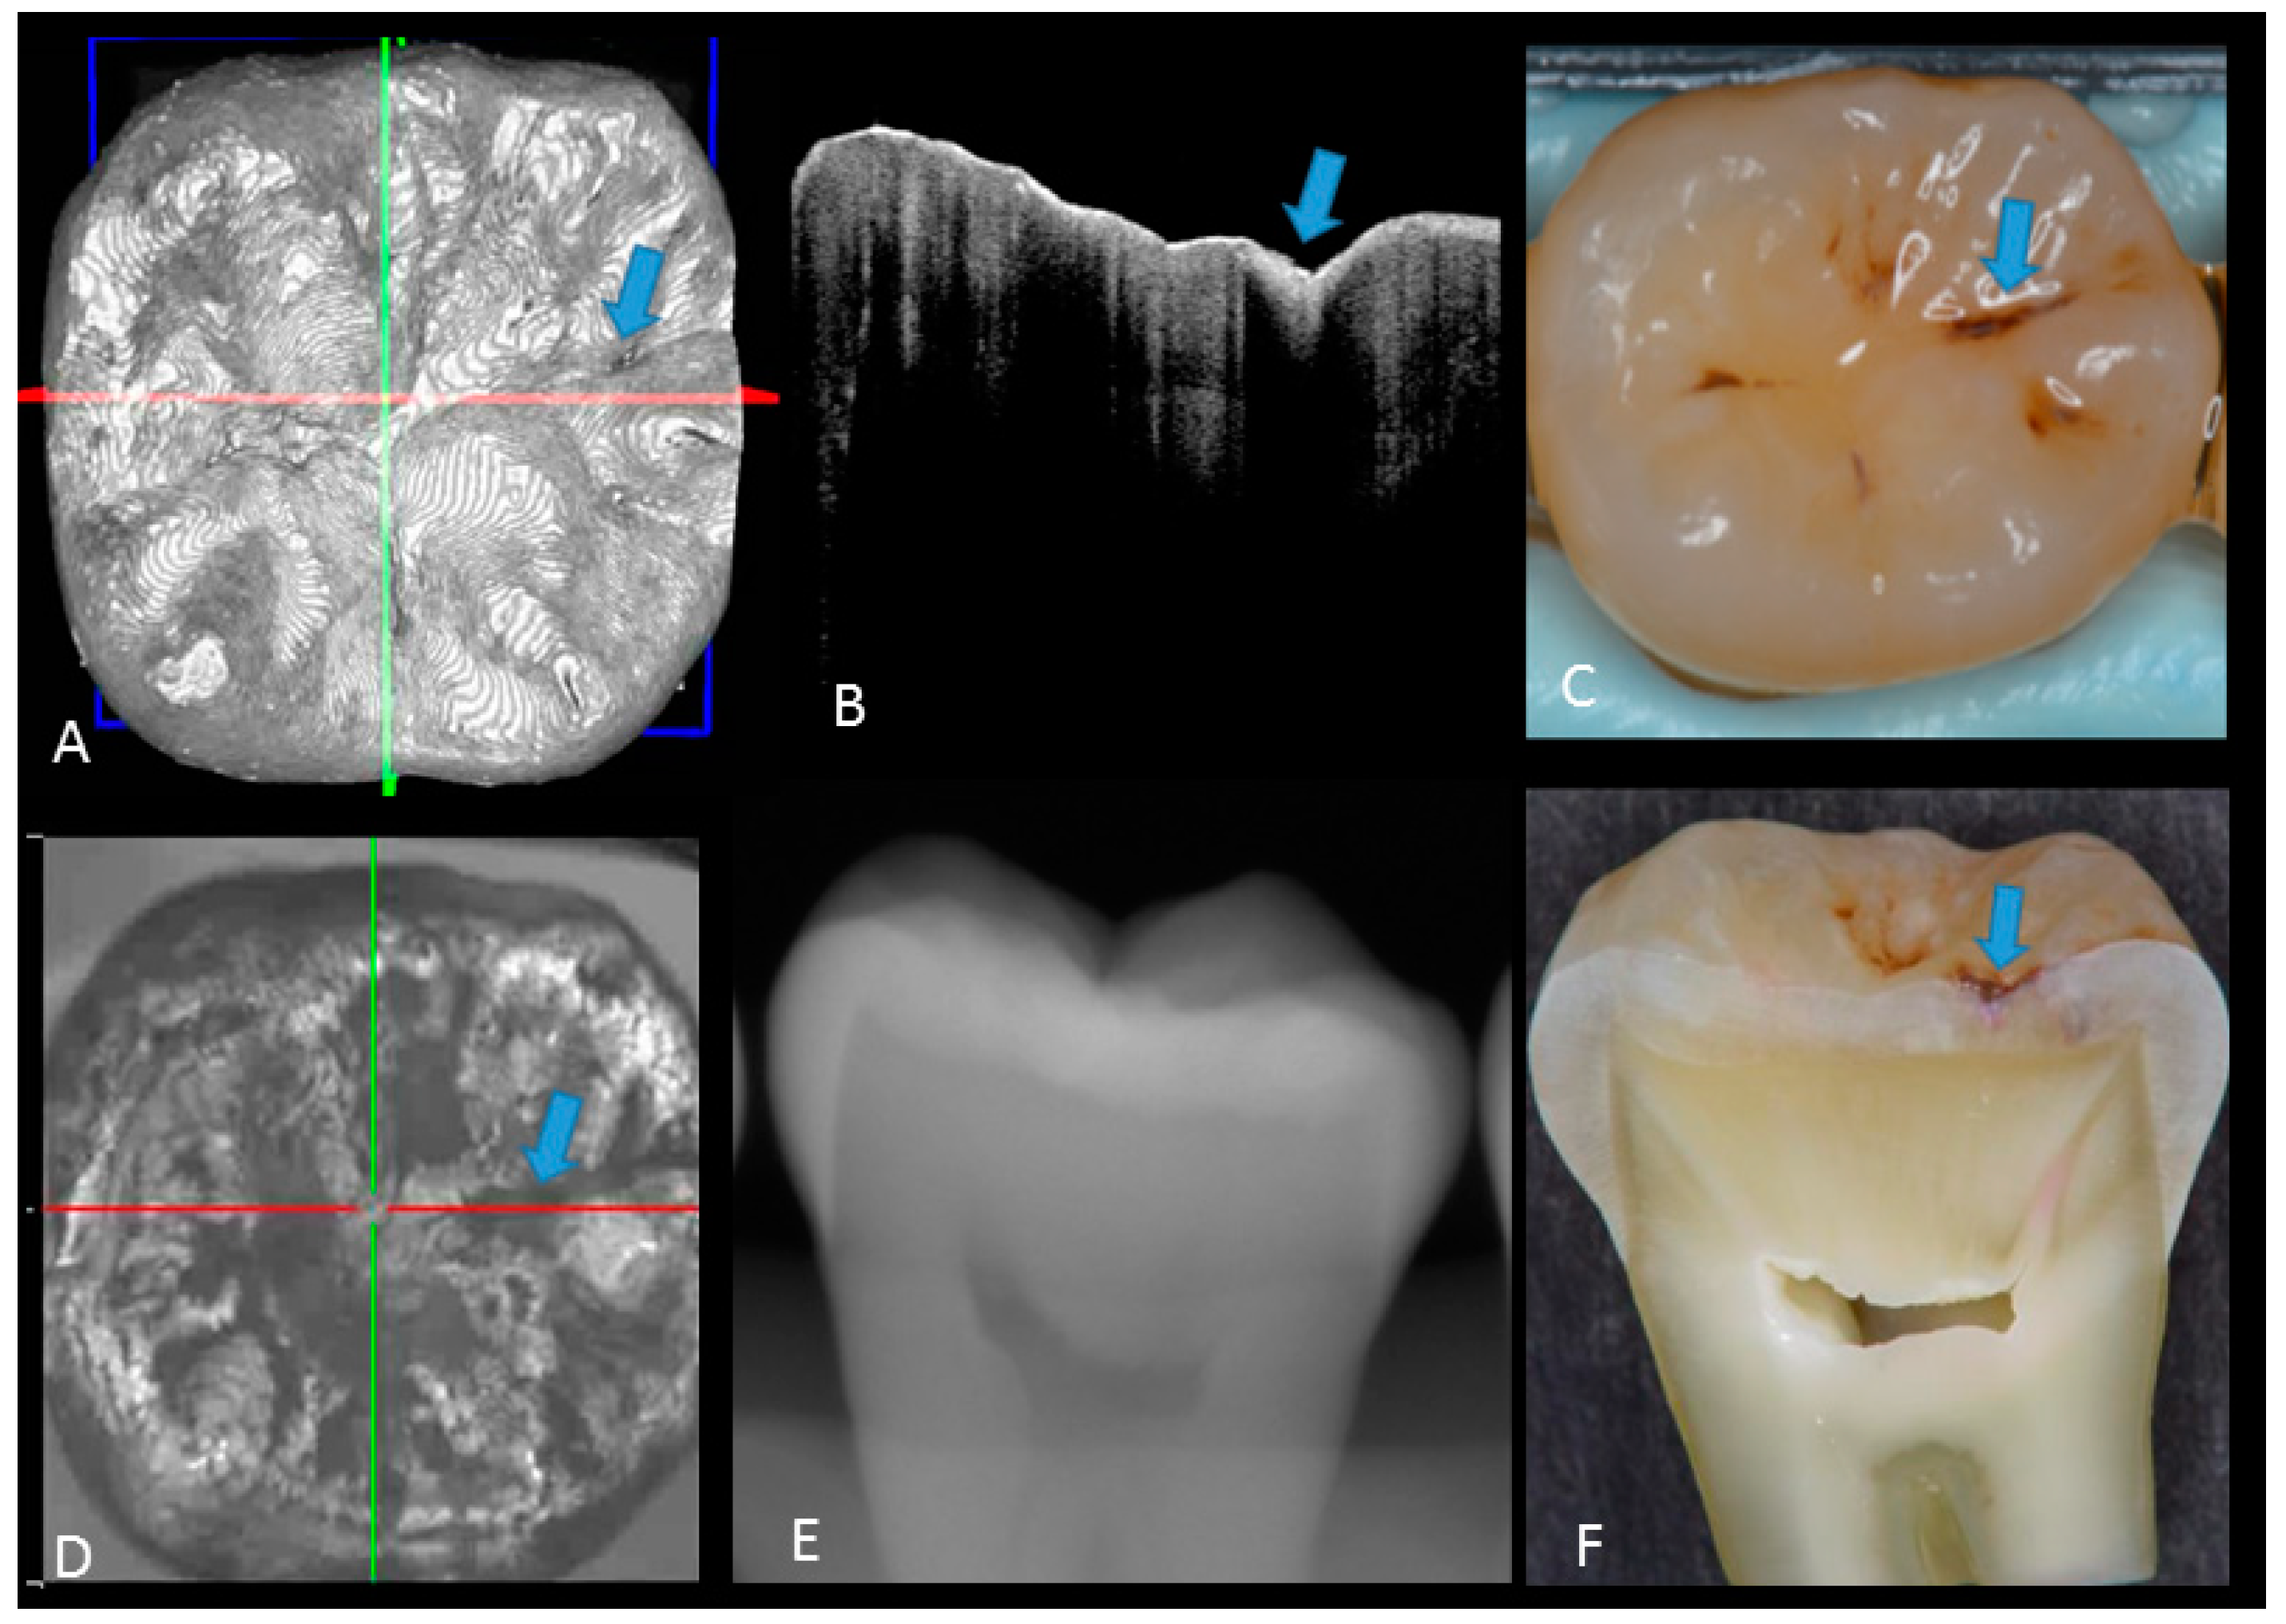

2. Materials and Methods

2.1. Specimen Preparation

2.2. Photography and X-ray Imaging

2.3. Optical Coherence Tomography

2.5. Validation of the Actual Scores